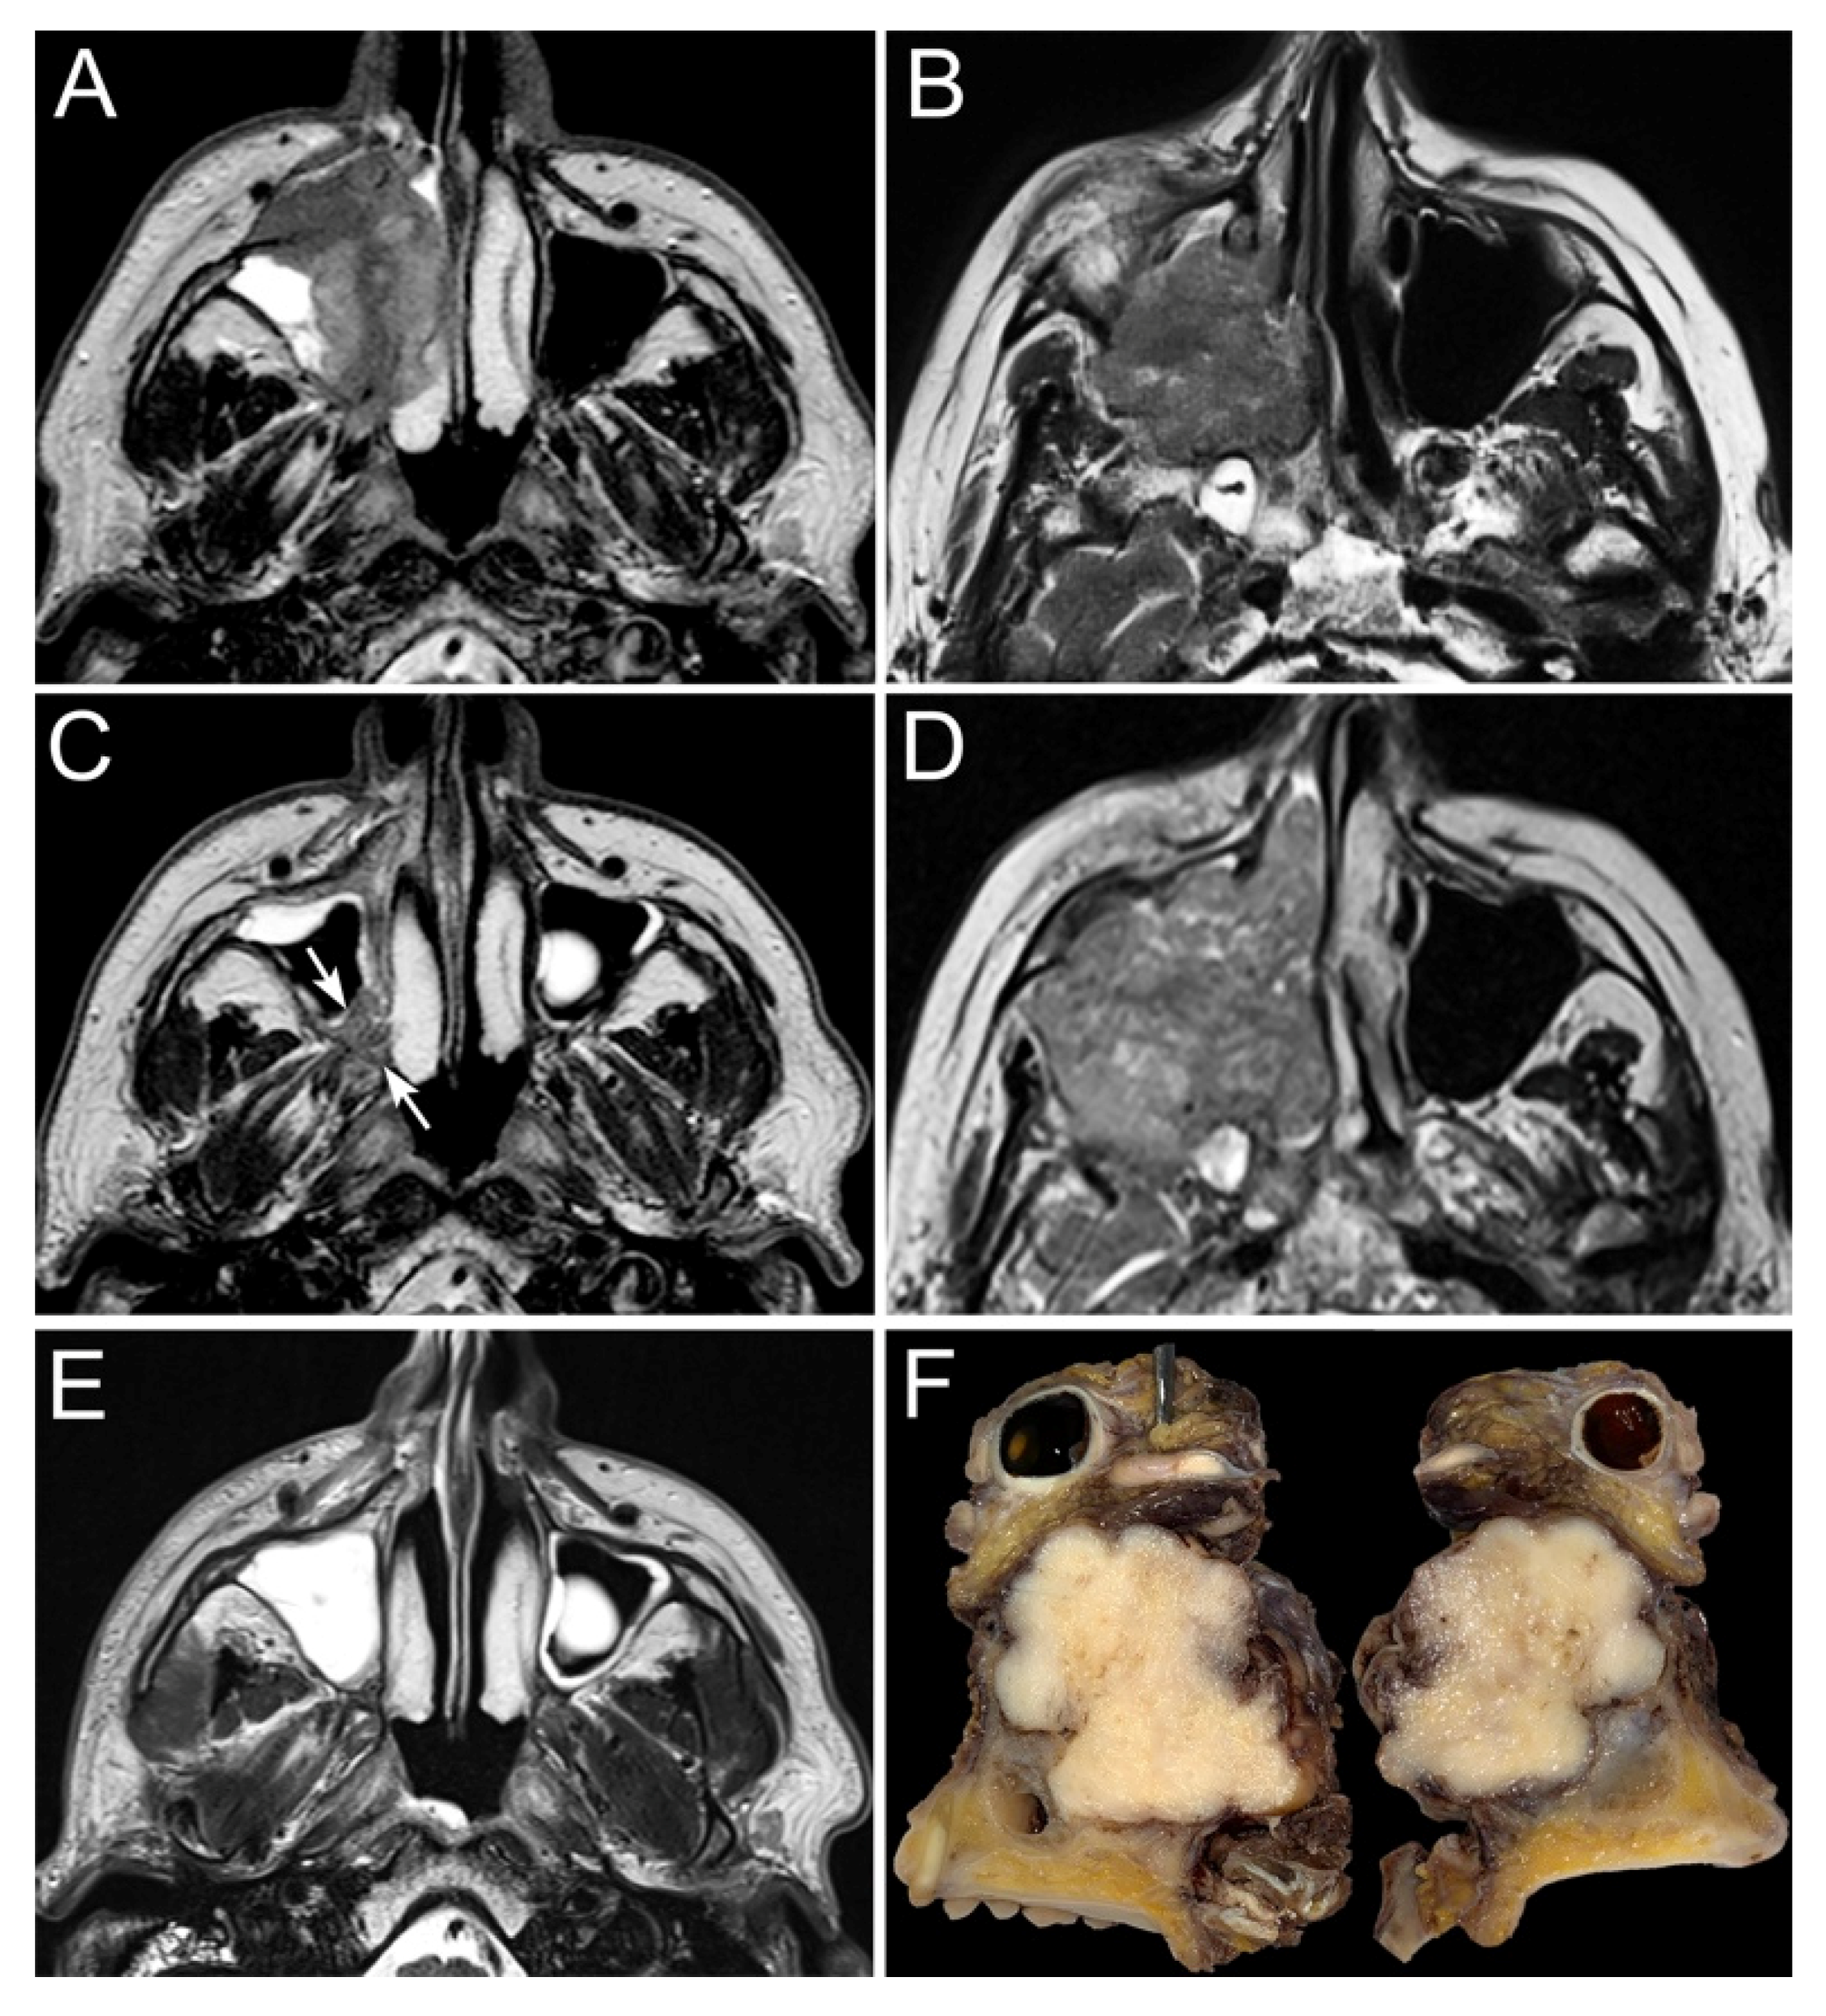

- Maroldi, R.; Borghesi, A.; Ravanelli, M.; Golemi, S.; Farina, D. The role of morphologic and functional imaging in pretreatment assessment. Adv. Otorhinolaryngol. 2020, 84, 28–45. [Google Scholar]

- Maroldi, R.; Farina, D.; Battaglia, G.; Maculotti, P.; Nicolai, P.; Chiesa, A. MR of malignant nasosinusal neoplasms frequently asked questions. Eur. J. Radiol. 1997, 24, 181–190. [Google Scholar] [CrossRef]

- Gencturk, M.; Ozturk, K.; Caicedo-Granados, E.; Li, F.; Cayci, Z. Application of diffusion-weighted MR imaging with ADC measurement for distinguishing between the histopathological types of sinonasal neoplasms. Clin. Imaging 2019, 55, 76–82. [Google Scholar] [CrossRef]